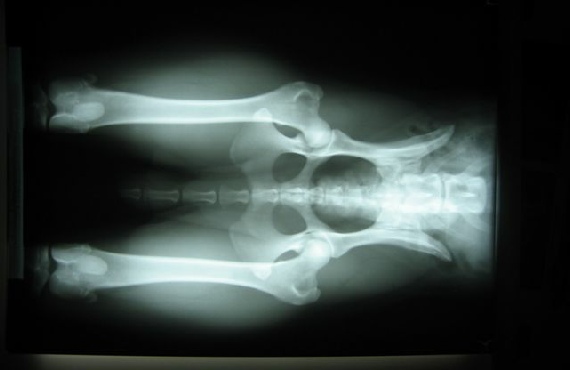

HD / ED RÖNTGENBILDER VON FACE

26.08.08 bekam ich eine Narkose (das fand ich gar nicht toll !!) , aber scheinbar sind diese Röntgenbilder, über meine Hüft- und Ellenbogengelenke, die dann gemacht wurden, ziemlich wichtig.